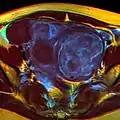

A relatively large submucosal leiomyoma; it fills out the major part of the endometrial cavity

MRI image with multiple uterine leiomiyomas